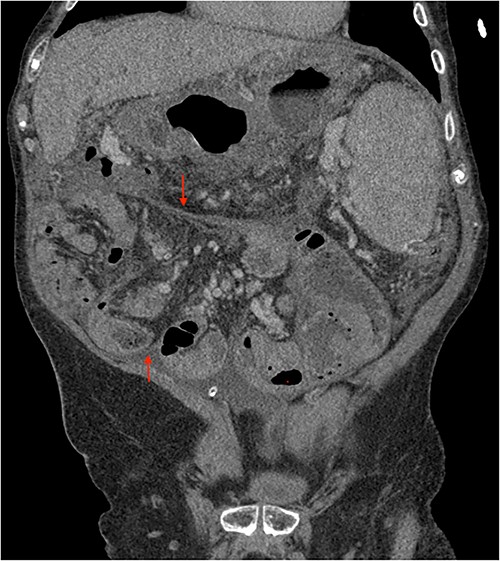

His clinical history and contrast-enhanced computed tomography (CT) findings (Figs 1–3) were compatible with EPS in Stage 4 (Table 2). Laboratory tests were non-specific, showing inflammation and malnutrition. He underwent nutritional support, corticosteroids and surgery. In surgery, fibrocollagenous membrane resection and enterolysis were done. Postoperative period was complicated by pneumonia treated with piperacillin+tazobactam and later bacterial peritonitis treated with ertapenem. The patient was discharged after 29 days with adequate nutrition and asymptomatic.

Portal phase coronal section image on CT showing loops wrapped in a membrane-like structure (arrow).

Imaging exams, mainly CT are important to evaluate causes of bowel obstruction [4]. Dilated or non-dilated small intestine loops may be wrapped in a membrane-like structure, proximal bowel dilatation, thickened peritoneum with diffuse or local calcification, and loculated ascites are some of the findings on CT [1, 12]. Barium X-ray provides a clue to bowel encapsulation, showing clustered loops of the small intestine in the center of the abdomen, known as the cauliflower sign [4]. Ultrasound and magnetic resonance imaging may give a clue but are rarely used [1, 12].